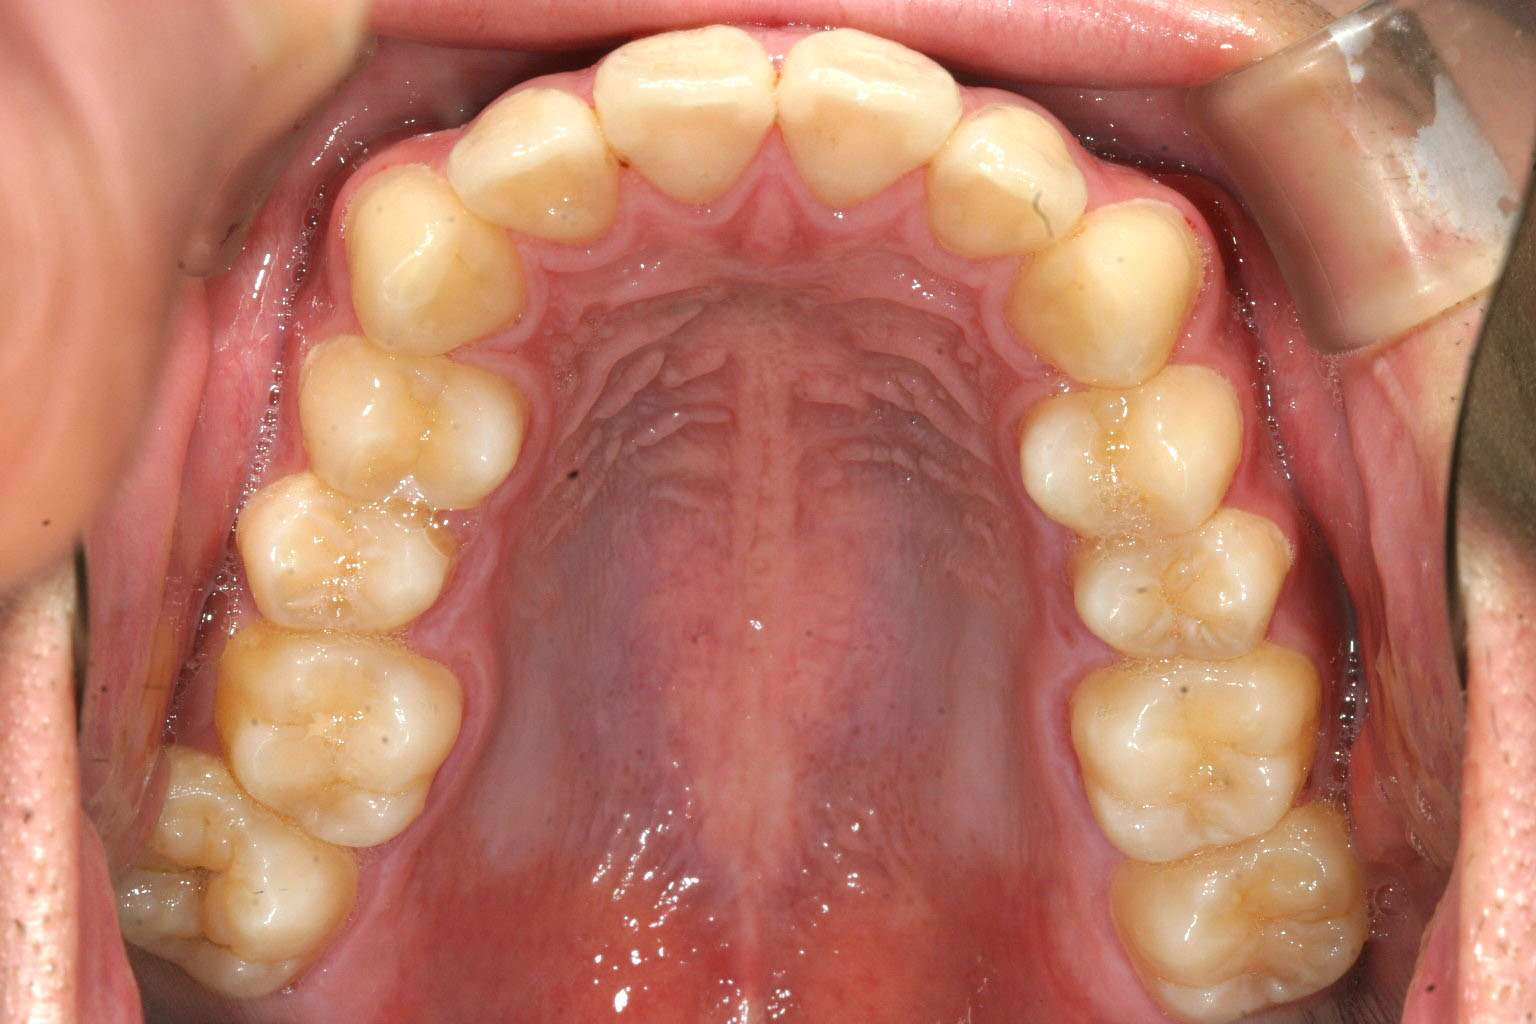

歯列が狭くなっている為前歯が出ています・

非抜歯で歯列のを広げました。